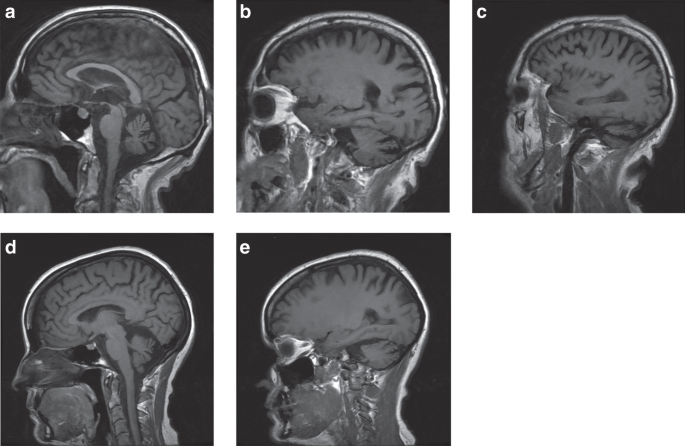

The index case, a 70-year-old man, presented with psychiatric symptoms, such as aggressive behavior, emotional indifference, and apathy at age 40. At first neurological examination at age 53, the Mini-Mental State Examination (MMSE) was 24/30 and a frontal syndrome was noted. There was no apraxia, aphasia, or memory loss. Neurological examination revealed an ataxic gait, dysmetria of the upper limbs, and cerebellar dysarthria. He stopped working at age 54. On follow-up at age 70, neuropsychological evaluation showed a severe CCAS. The frontal syndrome was at the forefront, with dorsolateral and orbitofrontal features. The patient had a severe dysexecutive syndrome (BREF 6/18) and affective deficits, with behavioral impairment and irritability. Moreover, the evaluation underlined attentional impairment with working memory deficits. Neurological examination showed ataxic gait, dysmetria of the four limbs, oculomotor signs with a saccadic pursuit and multidirectional nystagmus, and severe dysarthria without aphasia. The Scale for the Assessment and Rating of Ataxia (SARA) score was 26 (maximum worse score 40). There was no ptosis or ophthalmoplegia, or pyramidal syndrome or motor deficit. Cerebral magnetic resonance image (MRI) showed global cerebellar atrophy (Fig. 2).

(a–e) T1-weighted sagittal brain MRI slices. (a–c) Index case with atrophy of the cerebellum (a,b), vermis (a), and hemispheres (b) and no atrophy of the cortex (c). (d–e) Similar cerebellar atrophy in the second patient (his daughter).

The symptoms of his daughter, a 43-year-old woman, started at age 38 with dysarthria. She experienced a depressive syndrome for two years. Neuropsychological evaluation showed clear dysexecutive syndrome with a deficit in lexical access and slower information processing. Orbitofrontal features were also present, with apathy and emotional recognition impairment. Spatial cognition deficits were noted, with visual construction impairment. Other cognitive functions were preserved. Ocular movement recordings showed no cerebellar features but an increase of errors in the antisaccades test, suggestive of a frontal syndrome. There was no ptosis, ophthalmoplegia, or pyramidal signs. Her cerebral MRI also showed clear cerebellar atrophy (Fig. 2). As mentioned above a variant in AFG3L2 (p.A484P) was reported, as well as a variant in STUB1 (p.Y49C), which both segregated with the disease (Supplementary Fig. 1A).